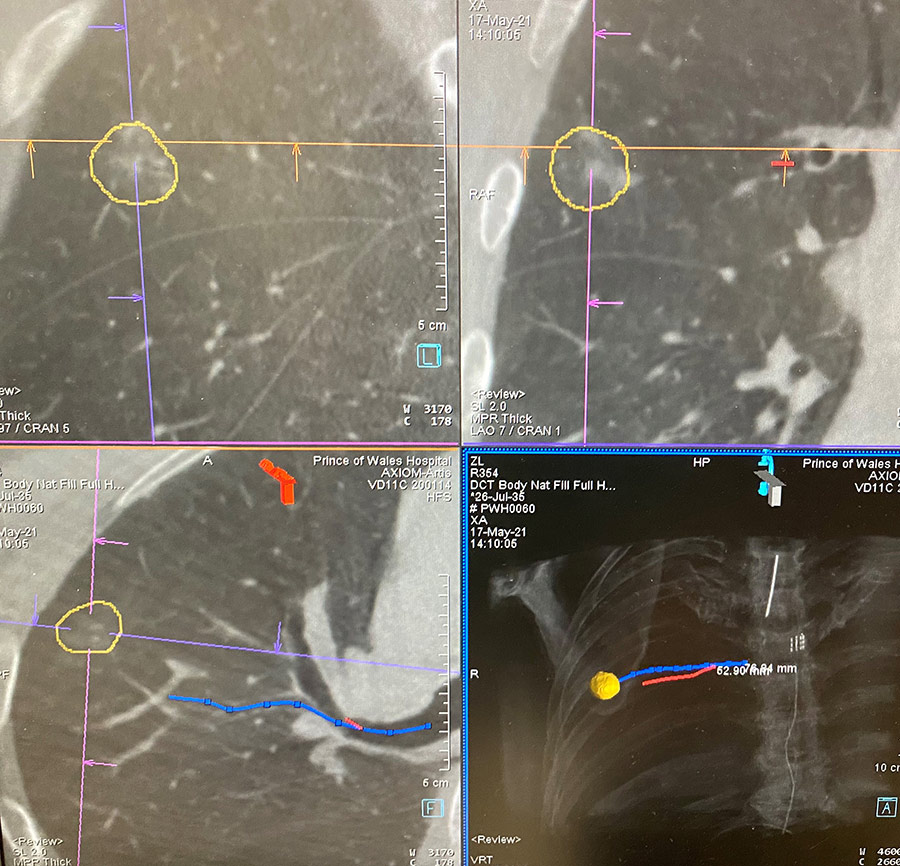

BMA混合操作室使用前沿CT扫描成像设备电磁导航支气管检查是一种先进支气管检查形式并配有GPS特征,外科医生精确定位天线切入肺癌并使用生成的微波能热消除恶性组织高风险外科病人或拒绝外科和放射理疗者可受益于这种独特的肺癌治疗

卡尔文博士和他的团队调查

多肺异位发现 患者有肝细胞癌历史BMA外科剖分解合并成混合战区单次操作解析有了适当的边缘癌症实现,所有肺部转移都成功处理混合战区BMA电磁导航为多项肺肿瘤运算法提供新帮助面向多路分点相容并关注肺功能的个人的一式处理选择

Calvin Ng博士及其团队共从25名病人中处理30个肺膜检测到100%技术成功率,某些结核需要同系双重烧损当前发现鼓励并证明研究应用BMA技术治疗肺癌有理反溯性调查证明支气管跨支气管微波烧损处理肺结核的安全和可行性还必须研究影响熔化区大小的关键因素,如肺延缩测量和水分测量本地控制率和生存率等长期结果对监控也很重要。跨支气流肺癌消退很可能成为个人化癌症治疗令人振奋的时代的重要资源,同时与语道内化疗或其他形式的跨支气流内分解术并发